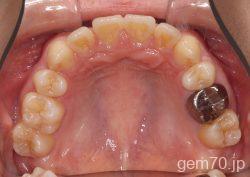

主訴)前歯のかみ合わせが深い

診断)過蓋咬合

使用装置)マルチブラケット装置(セラミックブラケット)

治療方法)4|4/4|4

治療期間) 2年8ヵ月 通院回数 32回